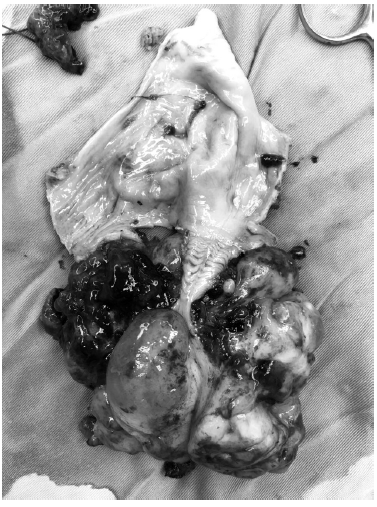

Con el diagnóstico ya mencionado se decide llevar a cirugía, donde se le realiza laparotomía exploratoria, toma de citología de líquido peritoneal, salpingooforectomía derecha, tumorectomía y omentectomía. En el transquirúrgico se evidencia una masa en la vagina que protruía a través del fondo de saco posterior de 10x12 cm., la cual se extirpa en su totalidad, no dejando lesión macroscópica visible.

El informe definitivo de patología mostró masa de vagina: sarcoma de bajo grado a favor de rabdomiosarcoma botrioide, tejido de ovario: tumor de células de Sertoly y Leydig de grado intermedio, omento: tejido fibroadiposo, citología de líquido peritoneal: negativo para malignidad.

La variedad botrioides (del griego botrys, racimo; eidos, aspecto) es la forma polipoide del rabdomiosarcoma embrionario. Se caracteriza por múltiples proyecciones polipoides que forman racimos de consistencia gelatinosa, friables y que se desprenden en fragmentos, ocasionando hemorragias a menudo. Los tumores de este tipo representan cerca de un 10% de todos los casos de rabdomiosarcoma y suelen ser tumores embrionarios que se desarollan bajo la superficie mucosa de orificios corporales como la vagina y la nariz; también se ha visto afectado el tracto biliar3.